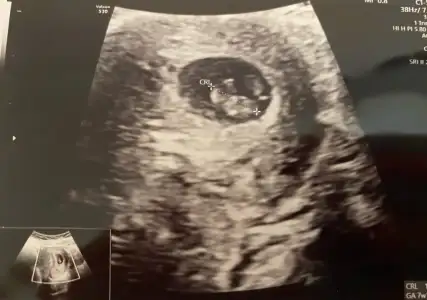

Nuba göre kız mı erkek mi sizce kızlar?

Bende yeniyim öncelikle☺️Mesajlarınızı dikkatle okudum bana da doktorum kesin birşey demedi 13.haftadayım yorumlar Mısınız acaba

Eklentiler